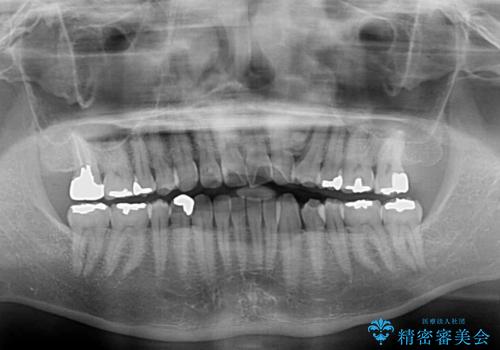

左上の犬歯が欠損しているため、正中の位置や奥歯の咬み合わせが理想的にならない点を了承していただきました。